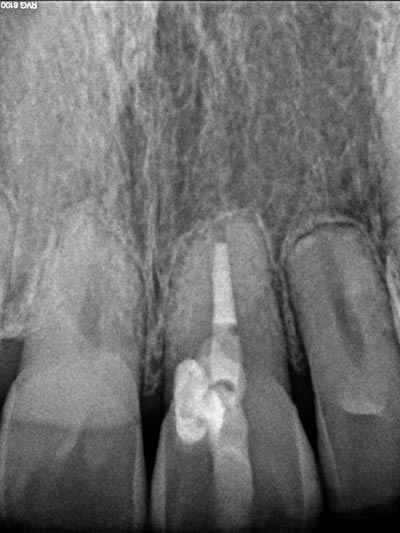

Imágenes: Endodoncia en un molar inferior izquierdo

Imágenes: Endodoncia en un incisivo inferior calcificado y necrótico.